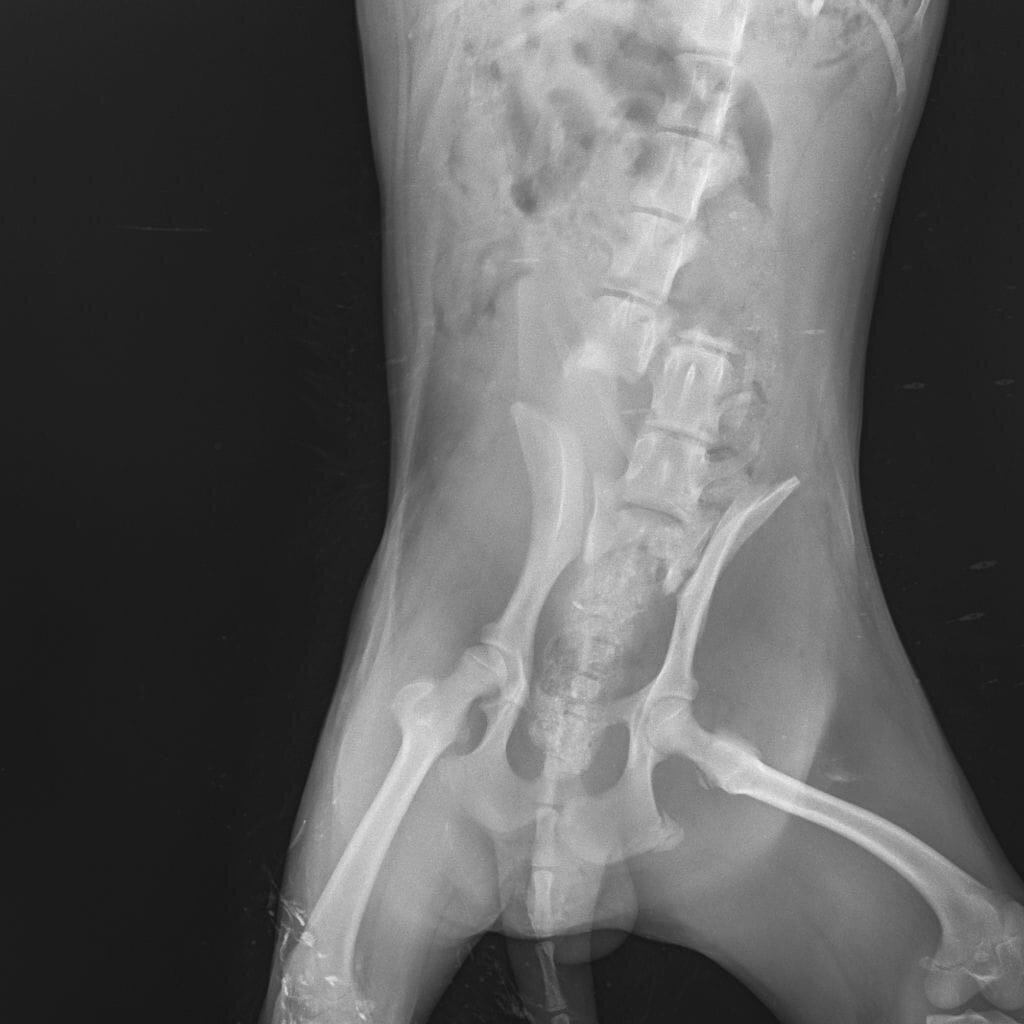

Осенью прошлого года пёсика нашли ползающим на передних лапках: оказалось, что у мальчика перелом поясничного отдела позвоночника со смещением и разрывом спинного мозга. Скорее всего, пёсик побывал под колёсами "железного монстра". Надежды на то, что хвостик сможет когда-то ходить, никакой не было. Но, мы не могли смотреть как малыш мучился от боли, и попытались ему помочь!

Никто не хотел вообще браться за эту операцию, только и слышали про усыпление. Мы не могли на это решится, глядя в глаза полные надежды, щеночек ждал нашей помощи…

Забрав в приют мальчика, мы стали ухаживать за ним. Несколько раз посещали хирурга и даже планировали провести операцию хвостику. Но со временем заметили, что Марк уже адаптировался к своему состоянию, а лишние вмешательства и стрессы ему совсем были ни к чему. Самое главное, что пёсик уже не испытывает боли.

Теперь Марк - наш постоянный житель, требующий особого ухода и внимания. Пёсик очень добрый и нежный хвостик, ему как воздух нужна любовь и защита человека.